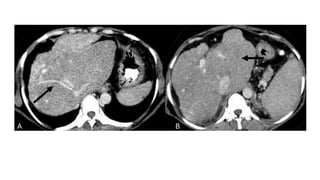

• Computed Tomography and Magnetic Resonance Imaging –

• The acute changes of increased sinusoidal pressure and hepatic

congestion due to outflow obstruction cause hepatomegaly with

patchy reduced enhancement in the peripheral portions of the liver on

the early phase of CECT and MRI with relatively increased

enhancement in the caudate lobe, which is enlarged.

• Reversal of enhancement with increased enhancement in the

peripheral portions of the liver and relative decreased enhancement in

the caudate lobe on the venous phase is termed the “flip flop”

phenomenon